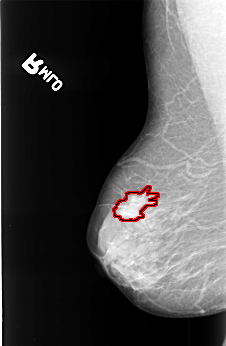

B_3395_1.RIGHT_MLO

RIGHT_MLO LINES 4496 PIXELS_PER_LINE 2936 BITS_PER_PIXEL 12 RESOLUTION 50 OVERLAY

FILE: B_3395_1.RIGHT_MLO.OVERLAY

TOTAL_ABNORMALITIES 1

ABNORMALITY 1

LESION_TYPE MASS SHAPE IRREGULAR-ARCHITECTURAL_DISTORTION MARGINS OBSCURED-SPICULATED

ASSESSMENT 4

SUBTLETY 3

PATHOLOGY MALIGNANT

TOTAL_OUTLINES 1

BOUNDARY